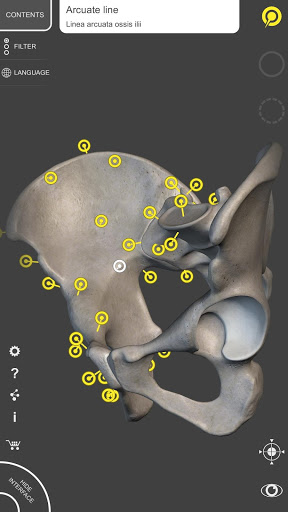

By selecting models or pins you will be shown the terms related to any specific anatomical part, you can select from 12 languages and show the terms in two languages simultaneously.

• Interactive Pin allow visualization of the term relative to every anatomical detail

MULTI-LANGUAGE

• The anatomical terms and the user interface are available in 12 languages: Latin, English, French, German, Italian, Portuguese, Russian, Spanish, Chinese, Japanese, Korean and Turkish

• The language can be selected directly from the interface of the app

• The anatomical terms can be shown in two languages simultaneously